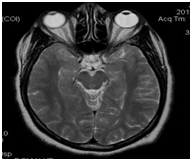

Anesthesiology is one of the medical specialties with greater technological and pharmacological advances, while it is also considered as high risk for both the professional and the patients. The anesthetic complications become even more important in tourist-patients as these people are far away from their home and a peri anesthetic mishap can mean drastic changes in the patient-family-friends planthat has been developed; from expensive hospital costs, high costs due to delays in the return trip, even death. The image 2 corresponds to a tourist-patient who traveled 6198 km and developed incidental post operative irreversible cortical blindness (Figure 2).

Figure 2  MRI showing post-anesthesia-surgery cortical edema in a tourist-patient. The blindness was permanent. With permission of www.anestesia-dolor.org